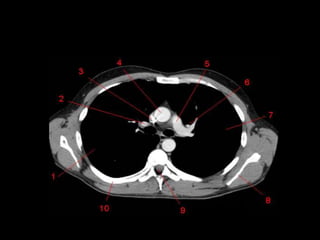

Mediastino Posterior

• Esôfago, aorta descendente, veias ázigo e

hemiázigo, ducto torácico e nervos

intercostais e autônomos.

Aorta Descendente

• Inicia em T4

pelo lado

esquerdo e

durante o

trajeto

caminha

para a

parte

posterior

ao esôfago.

Esôfago

• Posterior ou póstero-lateral à traquéia

• Lobos direito e esquerdo do pulmão se tocam

atrás do esôfago criando a Linha de Junção

Posterior.

• Antero-medial à aorta descendente

Sistema Azigo

• Ázigo: D

• Hemiázigo: E

– Se une em T9

• Póstero-lateral em relação a aorta

descendente.

• A veia ázigo curva-se sobre a face superior da

raiz do pulmão direito para se unir a VCS